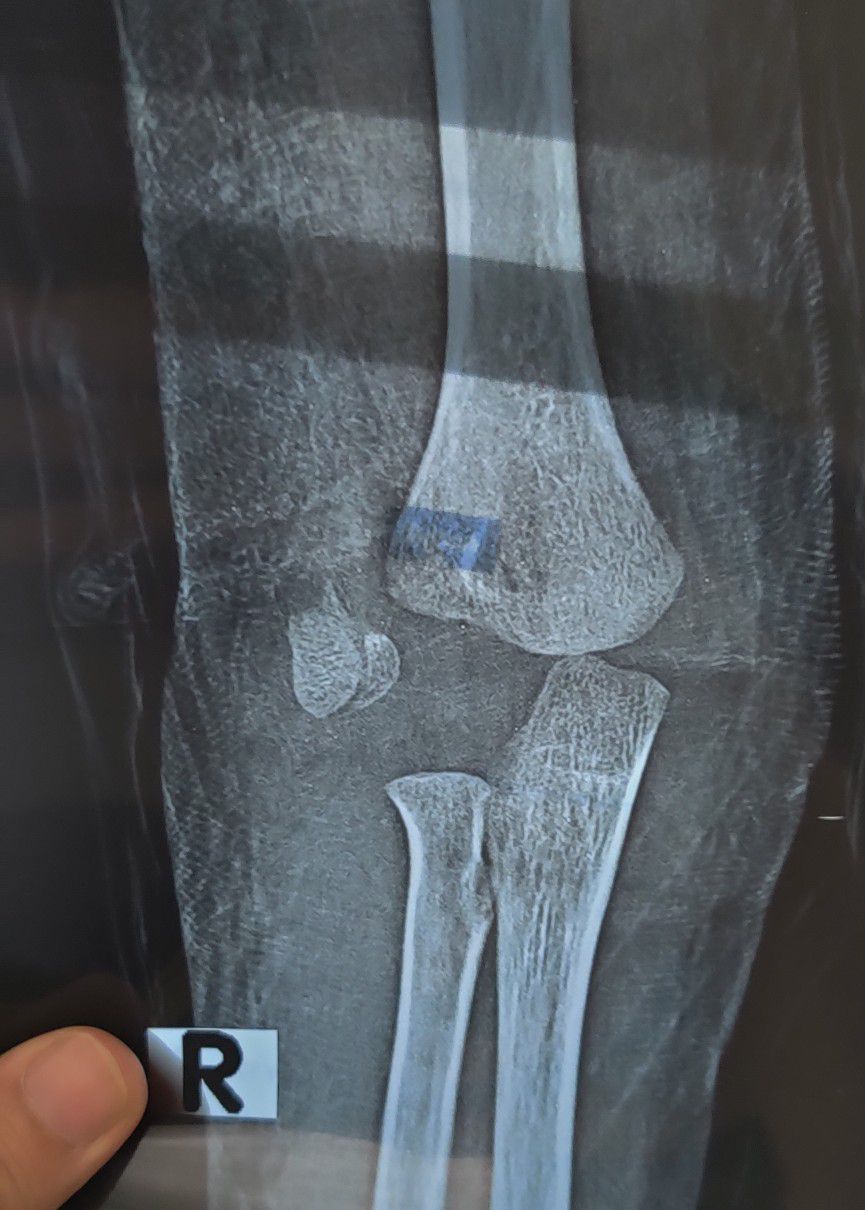

Fracture Capitellum & dislocation

Ortho

Ulna

Paeds

Capitellum